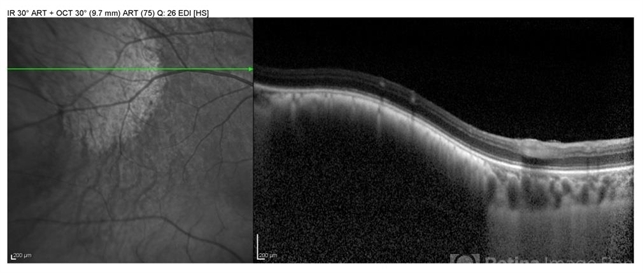

- optical coherence tomography (OCT), choroidal nevus

- EDI OCT imaging of a large pigmented choridal nevus showing mild elevation with no associated subretinal fluid.